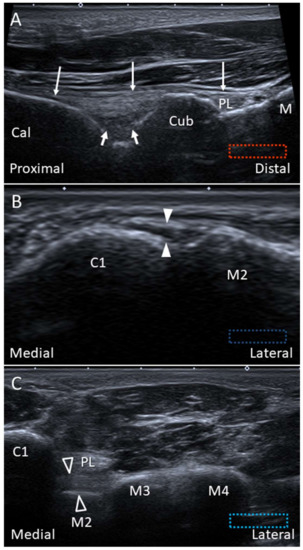

4.1. Peroneus Longus Tendon

4.1.1. Anatomy

4.1.2. Scanning Technique

4.1.3. Clinical Relevance